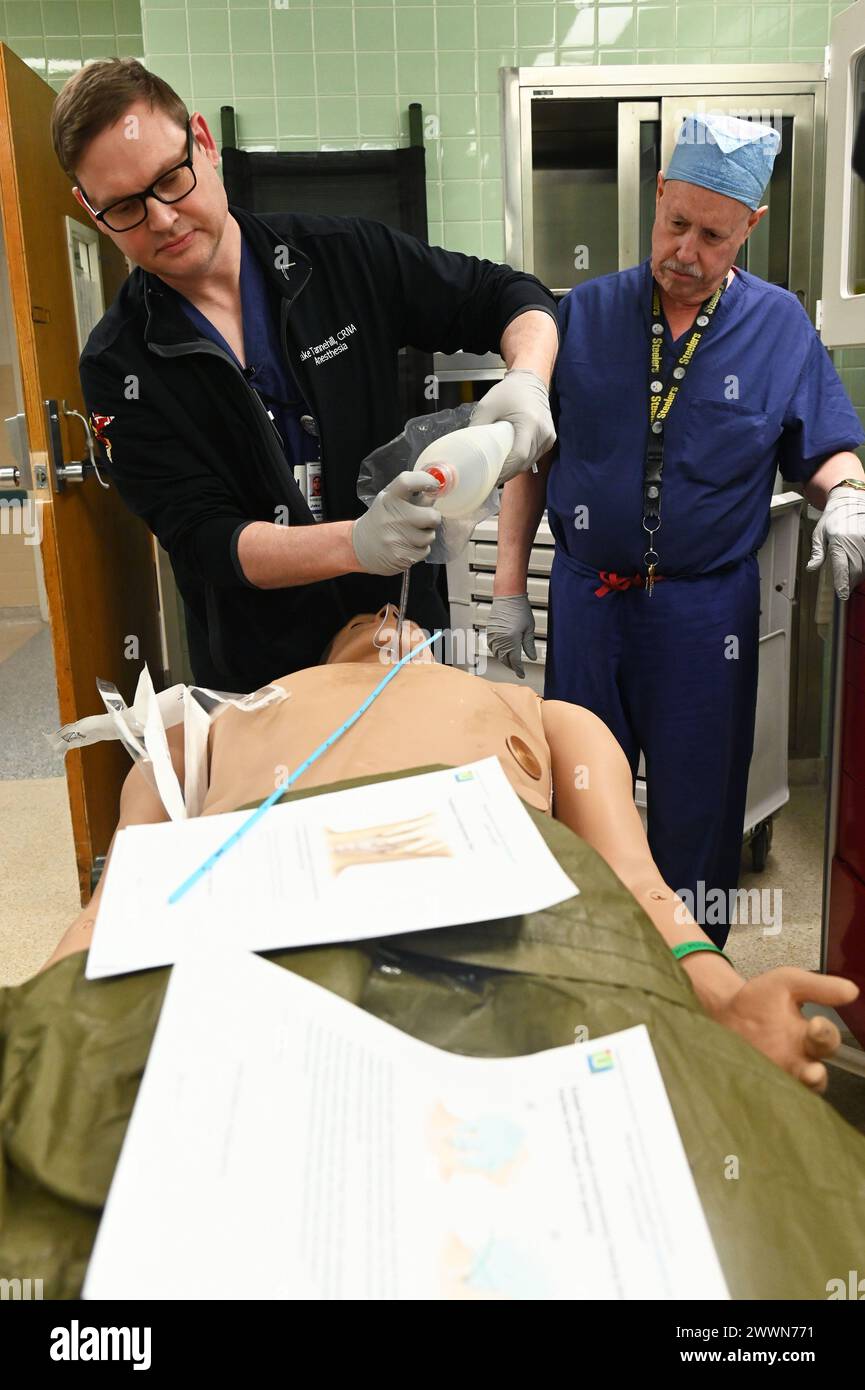

The Kimbrough Ambulatory Care Center Anesthesia Care Team simulated various methods of performing an emergency cricothyrotomy, Fort Meade, Maryland, Feb. 5, to validate providers' skills and update credentials. A cricothyrotomy is an incision made through the skin and cricothyroid membrane to establish a patent airway during certain life-threatening situations, such as airway obstruction by a foreign body, angioedema, or massive facial trauma. Defense Health Agency Stock Photohttps://www.alamy.com/image-license-details/?v=1https://www.alamy.com/the-kimbrough-ambulatory-care-center-anesthesia-care-team-simulated-various-methods-of-performing-an-emergency-cricothyrotomy-fort-meade-maryland-feb-5-to-validate-providers-skills-and-update-credentials-a-cricothyrotomy-is-an-incision-made-through-the-skin-and-cricothyroid-membrane-to-establish-a-patent-airway-during-certain-life-threatening-situations-such-as-airway-obstruction-by-a-foreign-body-angioedema-or-massive-facial-trauma-defense-health-agency-image600985198.html

The Kimbrough Ambulatory Care Center Anesthesia Care Team simulated various methods of performing an emergency cricothyrotomy, Fort Meade, Maryland, Feb. 5, to validate providers' skills and update credentials. A cricothyrotomy is an incision made through the skin and cricothyroid membrane to establish a patent airway during certain life-threatening situations, such as airway obstruction by a foreign body, angioedema, or massive facial trauma. Defense Health Agency Stock Photohttps://www.alamy.com/image-license-details/?v=1https://www.alamy.com/the-kimbrough-ambulatory-care-center-anesthesia-care-team-simulated-various-methods-of-performing-an-emergency-cricothyrotomy-fort-meade-maryland-feb-5-to-validate-providers-skills-and-update-credentials-a-cricothyrotomy-is-an-incision-made-through-the-skin-and-cricothyroid-membrane-to-establish-a-patent-airway-during-certain-life-threatening-situations-such-as-airway-obstruction-by-a-foreign-body-angioedema-or-massive-facial-trauma-defense-health-agency-image600985198.htmlRM2WWN6N2–The Kimbrough Ambulatory Care Center Anesthesia Care Team simulated various methods of performing an emergency cricothyrotomy, Fort Meade, Maryland, Feb. 5, to validate providers' skills and update credentials. A cricothyrotomy is an incision made through the skin and cricothyroid membrane to establish a patent airway during certain life-threatening situations, such as airway obstruction by a foreign body, angioedema, or massive facial trauma. Defense Health Agency

The Kimbrough Ambulatory Care Center Anesthesia Care Team simulated various methods of performing an emergency cricothyrotomy, Fort Meade, Maryland, Feb. 5, to validate providers' skills and update credentials. A cricothyrotomy is an incision made through the skin and cricothyroid membrane to establish a patent airway during certain life-threatening situations, such as airway obstruction by a foreign body, angioedema, or massive facial trauma. Defense Health Agency Stock Photohttps://www.alamy.com/image-license-details/?v=1https://www.alamy.com/the-kimbrough-ambulatory-care-center-anesthesia-care-team-simulated-various-methods-of-performing-an-emergency-cricothyrotomy-fort-meade-maryland-feb-5-to-validate-providers-skills-and-update-credentials-a-cricothyrotomy-is-an-incision-made-through-the-skin-and-cricothyroid-membrane-to-establish-a-patent-airway-during-certain-life-threatening-situations-such-as-airway-obstruction-by-a-foreign-body-angioedema-or-massive-facial-trauma-defense-health-agency-image600985589.html

The Kimbrough Ambulatory Care Center Anesthesia Care Team simulated various methods of performing an emergency cricothyrotomy, Fort Meade, Maryland, Feb. 5, to validate providers' skills and update credentials. A cricothyrotomy is an incision made through the skin and cricothyroid membrane to establish a patent airway during certain life-threatening situations, such as airway obstruction by a foreign body, angioedema, or massive facial trauma. Defense Health Agency Stock Photohttps://www.alamy.com/image-license-details/?v=1https://www.alamy.com/the-kimbrough-ambulatory-care-center-anesthesia-care-team-simulated-various-methods-of-performing-an-emergency-cricothyrotomy-fort-meade-maryland-feb-5-to-validate-providers-skills-and-update-credentials-a-cricothyrotomy-is-an-incision-made-through-the-skin-and-cricothyroid-membrane-to-establish-a-patent-airway-during-certain-life-threatening-situations-such-as-airway-obstruction-by-a-foreign-body-angioedema-or-massive-facial-trauma-defense-health-agency-image600985589.htmlRM2WWN771–The Kimbrough Ambulatory Care Center Anesthesia Care Team simulated various methods of performing an emergency cricothyrotomy, Fort Meade, Maryland, Feb. 5, to validate providers' skills and update credentials. A cricothyrotomy is an incision made through the skin and cricothyroid membrane to establish a patent airway during certain life-threatening situations, such as airway obstruction by a foreign body, angioedema, or massive facial trauma. Defense Health Agency

The Kimbrough Ambulatory Care Center Anesthesia Care Team simulated various methods of performing an emergency cricothyrotomy, Fort Meade, Maryland, Feb. 5, to validate providers' skills and update credentials. A cricothyrotomy is an incision made through the skin and cricothyroid membrane to establish a patent airway during certain life-threatening situations, such as airway obstruction by a foreign body, angioedema, or massive facial trauma. Defense Health Agency Stock Photohttps://www.alamy.com/image-license-details/?v=1https://www.alamy.com/the-kimbrough-ambulatory-care-center-anesthesia-care-team-simulated-various-methods-of-performing-an-emergency-cricothyrotomy-fort-meade-maryland-feb-5-to-validate-providers-skills-and-update-credentials-a-cricothyrotomy-is-an-incision-made-through-the-skin-and-cricothyroid-membrane-to-establish-a-patent-airway-during-certain-life-threatening-situations-such-as-airway-obstruction-by-a-foreign-body-angioedema-or-massive-facial-trauma-defense-health-agency-image600985568.html

The Kimbrough Ambulatory Care Center Anesthesia Care Team simulated various methods of performing an emergency cricothyrotomy, Fort Meade, Maryland, Feb. 5, to validate providers' skills and update credentials. A cricothyrotomy is an incision made through the skin and cricothyroid membrane to establish a patent airway during certain life-threatening situations, such as airway obstruction by a foreign body, angioedema, or massive facial trauma. Defense Health Agency Stock Photohttps://www.alamy.com/image-license-details/?v=1https://www.alamy.com/the-kimbrough-ambulatory-care-center-anesthesia-care-team-simulated-various-methods-of-performing-an-emergency-cricothyrotomy-fort-meade-maryland-feb-5-to-validate-providers-skills-and-update-credentials-a-cricothyrotomy-is-an-incision-made-through-the-skin-and-cricothyroid-membrane-to-establish-a-patent-airway-during-certain-life-threatening-situations-such-as-airway-obstruction-by-a-foreign-body-angioedema-or-massive-facial-trauma-defense-health-agency-image600985568.htmlRM2WWN768–The Kimbrough Ambulatory Care Center Anesthesia Care Team simulated various methods of performing an emergency cricothyrotomy, Fort Meade, Maryland, Feb. 5, to validate providers' skills and update credentials. A cricothyrotomy is an incision made through the skin and cricothyroid membrane to establish a patent airway during certain life-threatening situations, such as airway obstruction by a foreign body, angioedema, or massive facial trauma. Defense Health Agency

The Kimbrough Ambulatory Care Center Anesthesia Care Team simulated various methods of performing an emergency cricothyrotomy, Fort Meade, Maryland, Feb. 5, to validate providers' skills and update credentials. A cricothyrotomy is an incision made through the skin and cricothyroid membrane to establish a patent airway during certain life-threatening situations, such as airway obstruction by a foreign body, angioedema, or massive facial trauma. Defense Health Agency Stock Photohttps://www.alamy.com/image-license-details/?v=1https://www.alamy.com/the-kimbrough-ambulatory-care-center-anesthesia-care-team-simulated-various-methods-of-performing-an-emergency-cricothyrotomy-fort-meade-maryland-feb-5-to-validate-providers-skills-and-update-credentials-a-cricothyrotomy-is-an-incision-made-through-the-skin-and-cricothyroid-membrane-to-establish-a-patent-airway-during-certain-life-threatening-situations-such-as-airway-obstruction-by-a-foreign-body-angioedema-or-massive-facial-trauma-defense-health-agency-image600987065.html

The Kimbrough Ambulatory Care Center Anesthesia Care Team simulated various methods of performing an emergency cricothyrotomy, Fort Meade, Maryland, Feb. 5, to validate providers' skills and update credentials. A cricothyrotomy is an incision made through the skin and cricothyroid membrane to establish a patent airway during certain life-threatening situations, such as airway obstruction by a foreign body, angioedema, or massive facial trauma. Defense Health Agency Stock Photohttps://www.alamy.com/image-license-details/?v=1https://www.alamy.com/the-kimbrough-ambulatory-care-center-anesthesia-care-team-simulated-various-methods-of-performing-an-emergency-cricothyrotomy-fort-meade-maryland-feb-5-to-validate-providers-skills-and-update-credentials-a-cricothyrotomy-is-an-incision-made-through-the-skin-and-cricothyroid-membrane-to-establish-a-patent-airway-during-certain-life-threatening-situations-such-as-airway-obstruction-by-a-foreign-body-angioedema-or-massive-facial-trauma-defense-health-agency-image600987065.htmlRM2WWN93N–The Kimbrough Ambulatory Care Center Anesthesia Care Team simulated various methods of performing an emergency cricothyrotomy, Fort Meade, Maryland, Feb. 5, to validate providers' skills and update credentials. A cricothyrotomy is an incision made through the skin and cricothyroid membrane to establish a patent airway during certain life-threatening situations, such as airway obstruction by a foreign body, angioedema, or massive facial trauma. Defense Health Agency